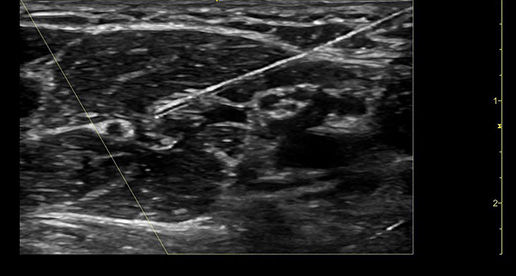

Improved visualization with Needle Recognition

Needle Recognition also allows you to easily differentiate between the needle and patient anatomy with confidence—allowing you to quickly guide the needle exactly where it needs to be and helping to minimize patient discomfort.